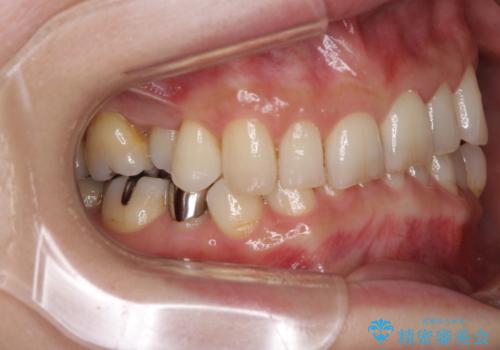

- 奥歯が咬めないくらいに痛いとのことで来院された患者様です。

痛みの強い歯は、歯髄組織が強い炎症を起こしており、神経を取り除く必要であったため、速やかに根管治療を行いました。

その後、オールセラミッククラウンにて補綴治療を行う予定でしたが、処置した歯以外にも治療が必要と思われる歯があったり、デコボコした歯列も気になるとのことで、患者様希望によりインビザラインにてマウスピース矯正を行うこととしました。

まずは矯正治療前に必要なむし歯処置を行い、その後矯正治療を行ってから、最後にオールセラミッククラウンなどで補綴治療を行うこととしました。

咬合力が非常に強く、全体的に歯が擦り減っている状態であったので、理想的な咬み合わせを達成することは難しく、また咬合力が強い方のマウスピース矯正は、思い通りに動かないことがあるため、ワイヤー矯正の方が望ましいように思えました。